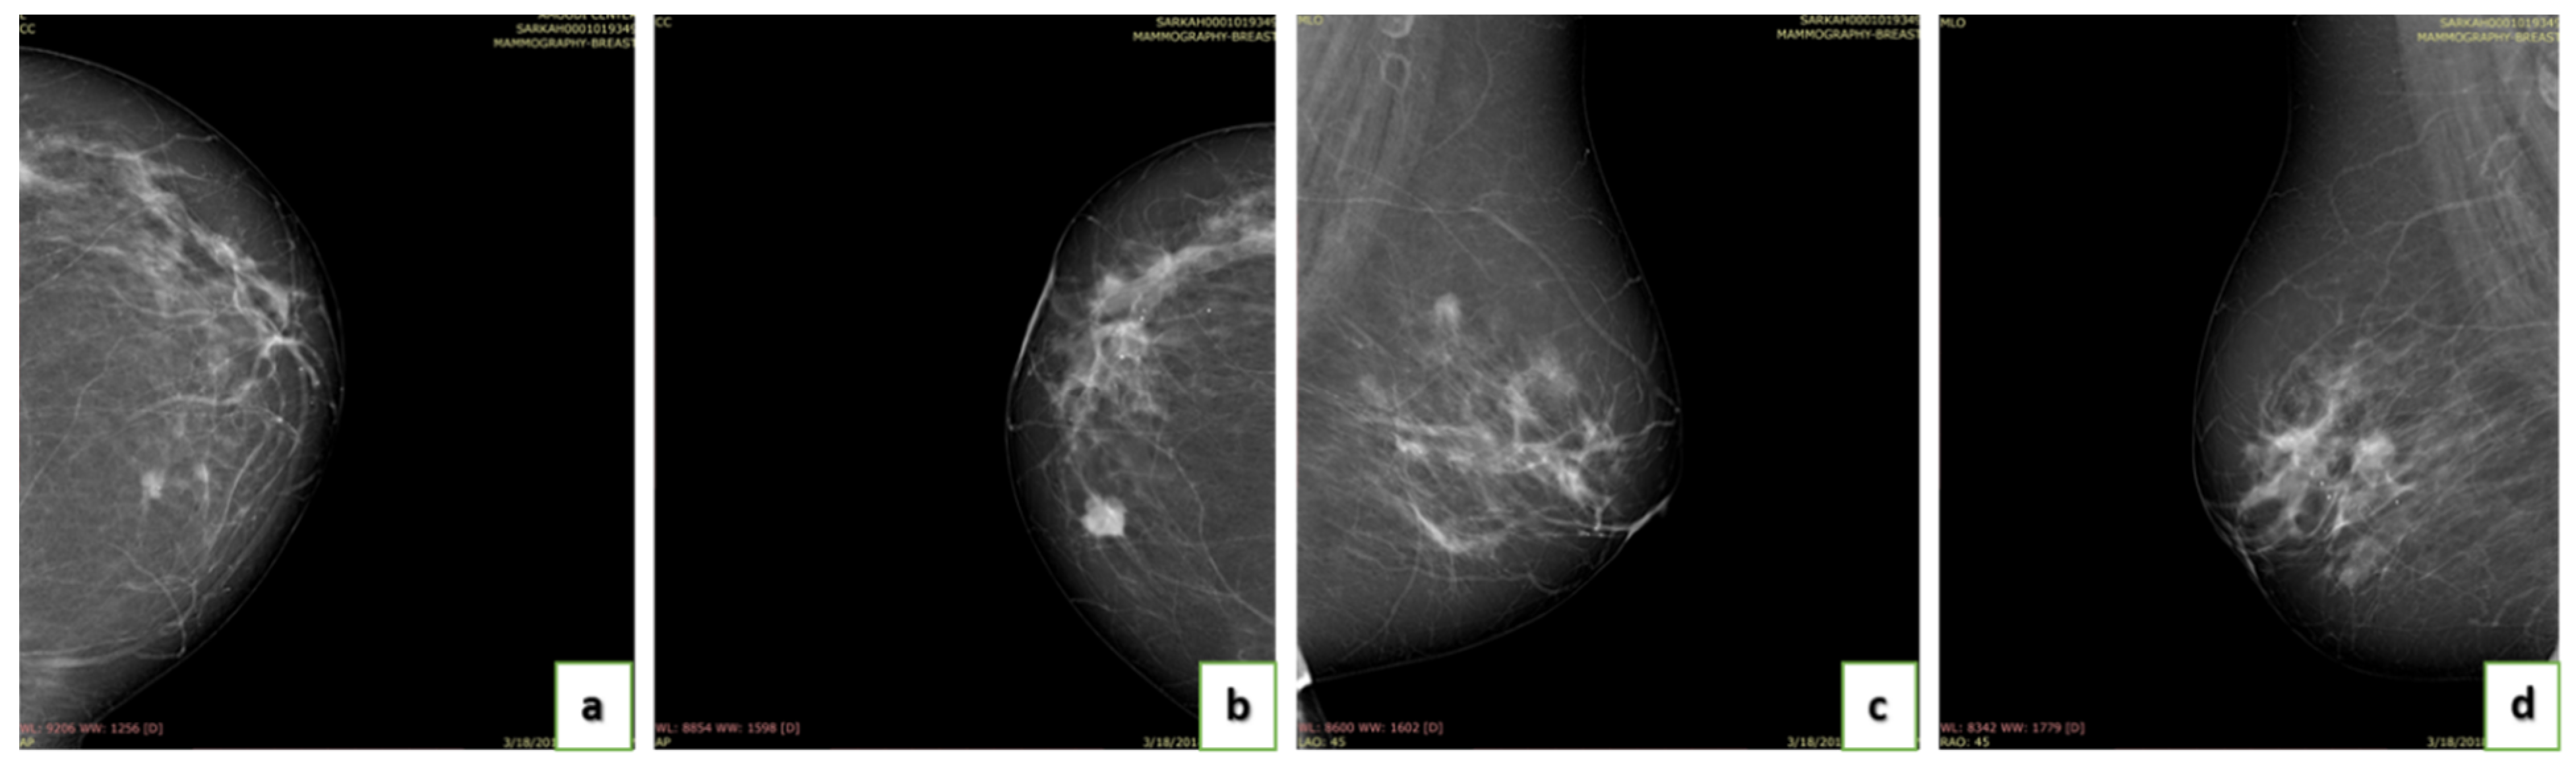

4.4. Breast Density

- A (0–25%): Almost entirely fatty indicates that the breasts are almost entirely composed of fat. One out of ten women has this result.

- B (25–50%): Scattered areas of fibroglandular density indicate some scattered areas of density, but most of the breast tissue is non-dense. Four out of ten women have this result.

- C (50–75%): Heterogeneously dense indicates that there are some areas of non-dense tissue but that most of the breast tissue is dense. Four out of ten women have this result.

- D (75–100%): Extremely dense indicates that nearly all breast tissue is dense. One out of each women has this result.